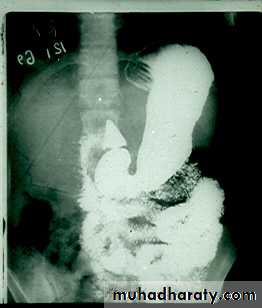

Narrowing :

the narrowing is Constant Short length (confined to cardia).

Regular and smooth.

No shouldering sign.

Tapering (Tip of pencil , cigar shape) Under left dome of diaphragm.

DILATATION (Sac like in proximal part )

Undulating or spiky out line due to sluggish peristalsis.

Non- homogeneity of Barium due to food particles.

Air Barium level.